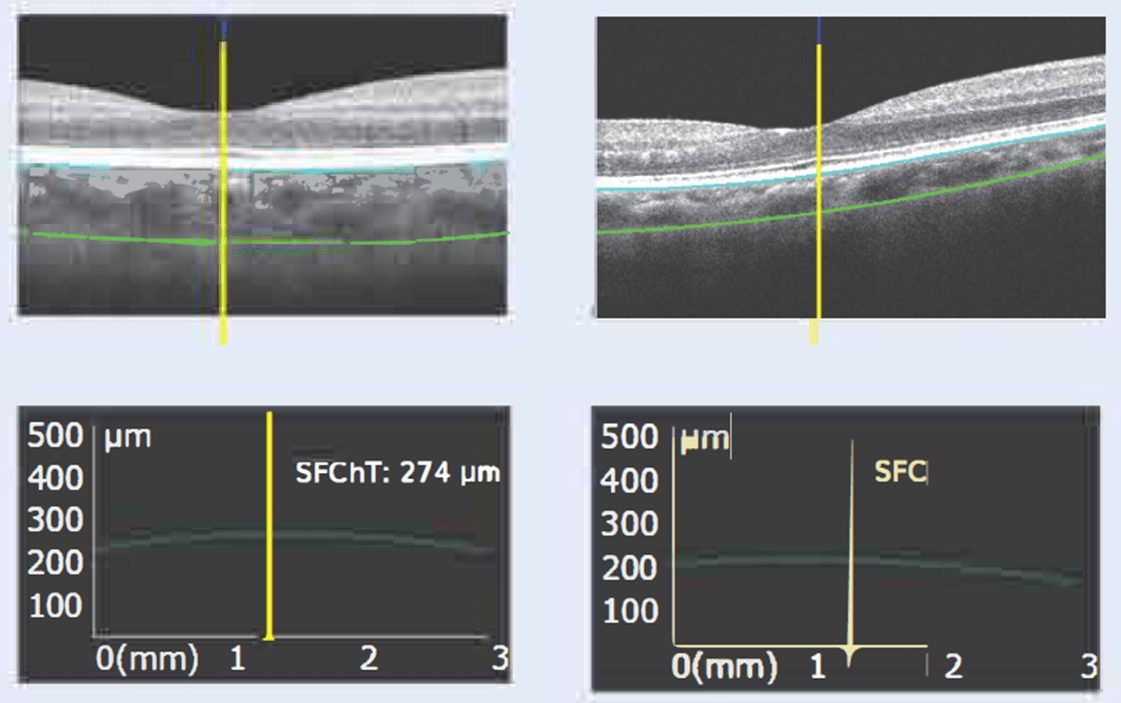

Аналіз судинної оболонки

Дослідження показують, що в очах молодих людей з високим ступенем міопії часто спостерігається тонша судинна оболонка, що робить її оцінку важливою частиною лікування. Colombo IOL забезпечує високоякісні ОСТ-зображення та точне вимірювання субфовеальної товщини судинної оболонки (SFChT) для детального аналізу.